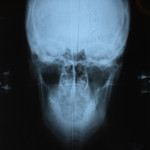

If it’s your first time to go to an upper cervical chiropractor, you’ll need an average of 8 to 12 visits, then the doctor will re-assess you for lifetime treatment. The first session involves a general assessment of your health, habits, and posture, followed by three x-rays (from the side, front, and top of head and neck) specific to the practice of upper cervical chiropractic. This is usually the longest session. The doctor will then study your x-rays, posture, and result of the initial consultation, and based on all these will determine if you need an atlas or spine adjustment on your next visit.

Front of head